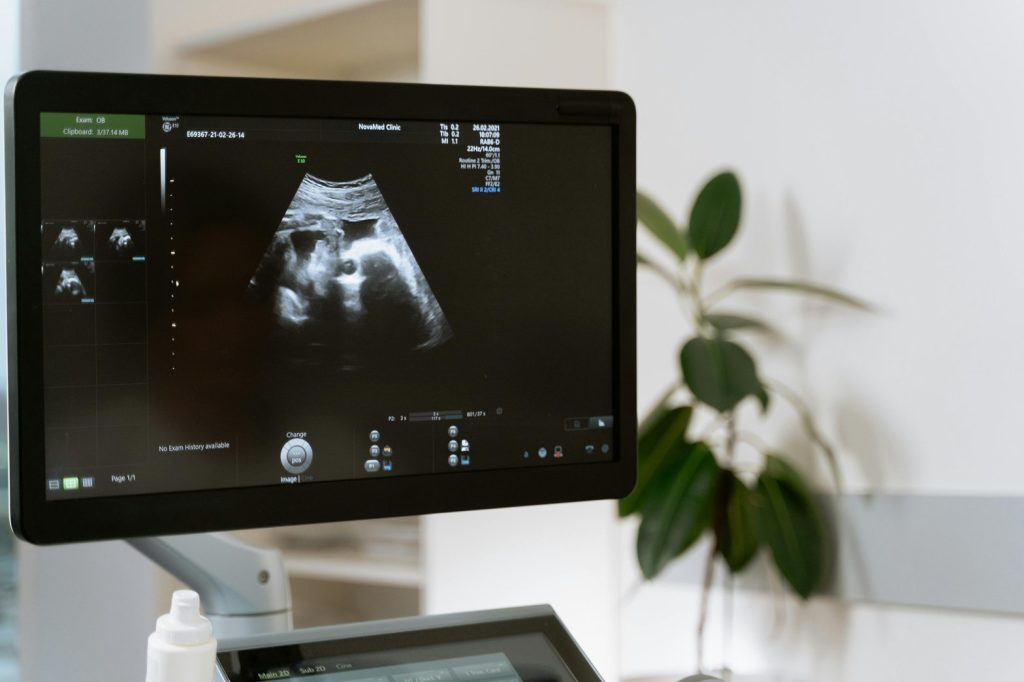

Picture this: a painless, radiation-free scan that can look inside your body in real time. From monitoring pregnancies to detecting heart problems, ultrasound radiology quietly powers millions of diagnoses every year. As the Cleveland Clinic notes, ultrasound radiology is a medical imaging procedure that utilizes high-frequency sound waves to generate cross-sectional images of internal body structures, including soft tissues and blood vessels.

This procedure is safe and non-invasive since it does not use radiation. Per Investigative Radiology, the test is ideal for imaging children and pregnant women as it does not expose them to radiation that can later lead to complications like cancer. Ultrasound is one of the most useful tools for accurate diagnosis, according to the World Health Organization.

Ultrasound radiology stands out as an exceptionally safe, affordable and versatile diagnostic tool in modern medicine. Unlike X-rays or CT scans, ultrasound provides critical, real-time internal insight into organs and soft tissues without any radiation exposure, making it ideal for procedures like monitoring pregnancies.